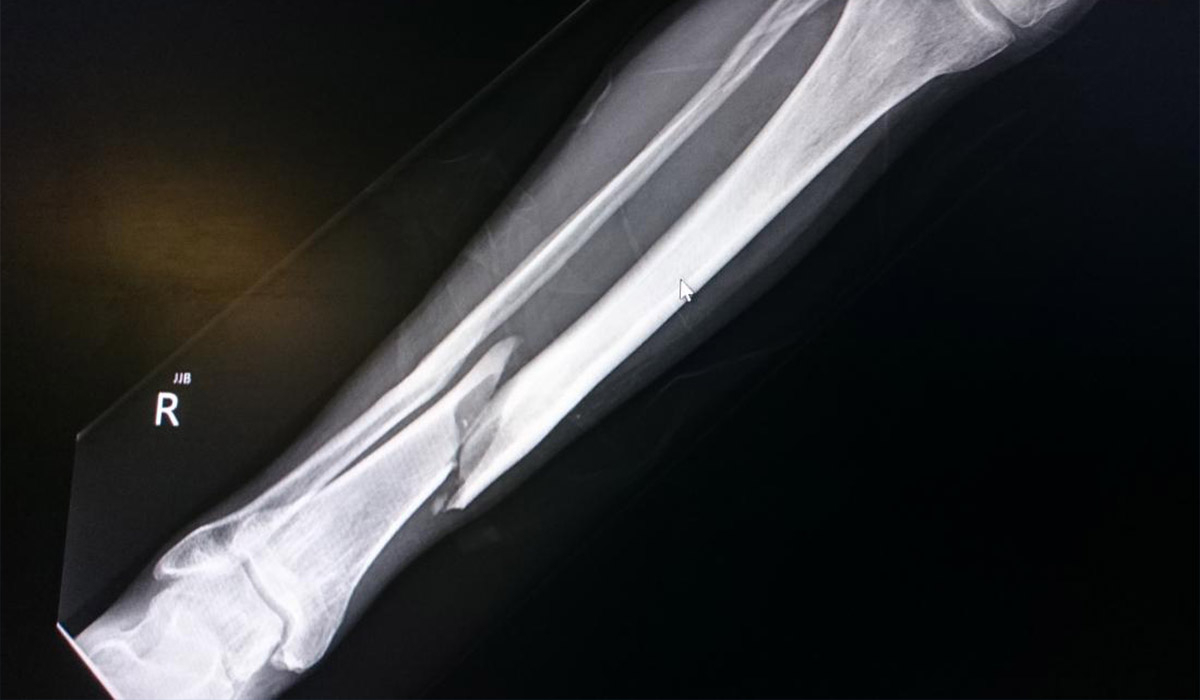

Одним із найефективніших та найсучасніших малоінвазивних методів лікування переломів гомілки є блокуючий інтрамедулярний остеосинтез (БІОС).

Під час операції здійснюється невеликий розріз шкіри вище чи нижче місця перелому під контролем рентгенапарату. Всередину кістки вводиться титановий або сталевий стержень.

Така фіксація кістки дуже міцна та мобільна.